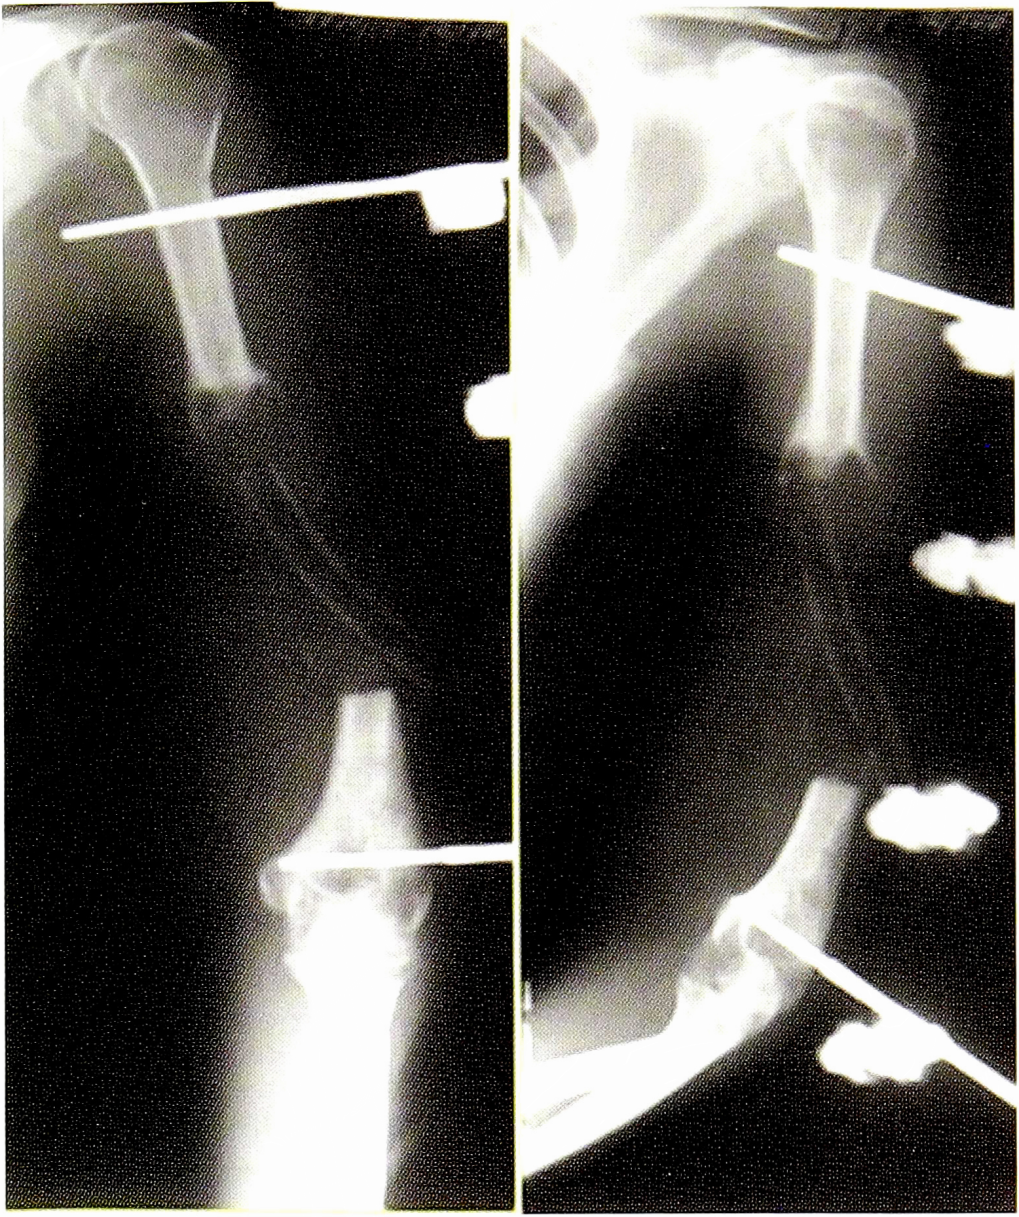

Рис. 4. Рентгенограмма пациентки И. до операции.

Fig. 4. Radiograph of patient I. before surgery.

Рис. 6. Рентгенограммы пациентки И. после удаления цементного спейсера.

Fig. 6. Radiographs of patient I. after removal of cement spacer.

Рис. 8. Рентгенограммы пациентки И. через год после операции.

Fig. 8. Radiographs of the patient I. a year after surgery.